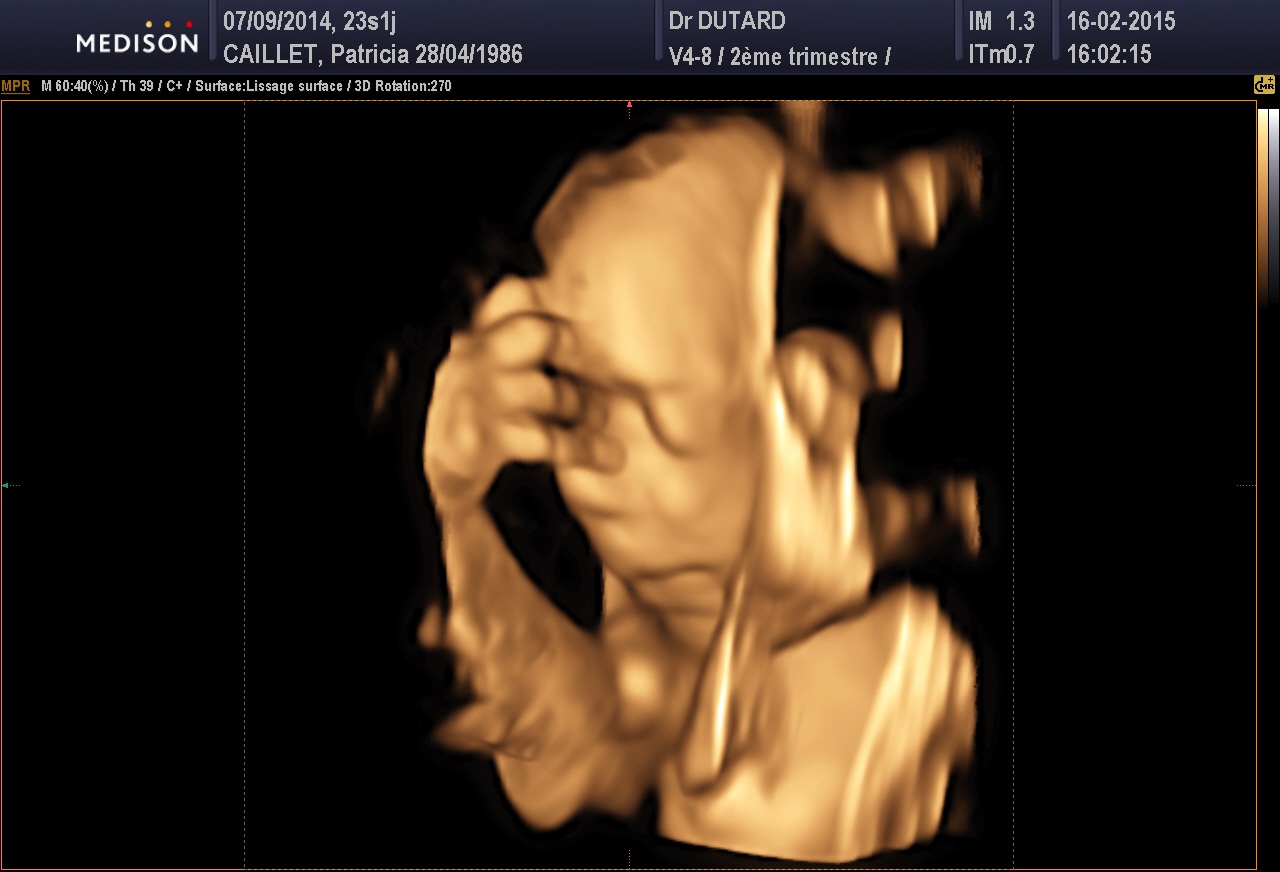

de son ptit bonhomme,puis on s en lasse pas de regarder ses echo surtout en 3d c est le top